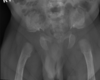

Mieloma Múltiplo

Quarta década

Vértebras, costelas, crânio, ombro e pelve

Pode apresentar como múltiplas lesões osteolíticas com recorte endosteal ou osteopenia generalizada com fraturas compressivas patológicas nas vértebras (poupa pedículo).